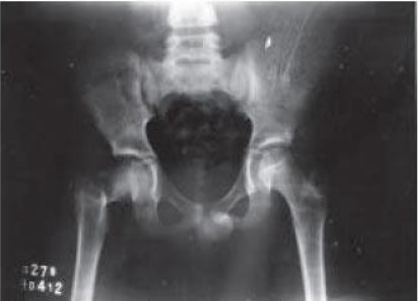

Com base na classificação de Delbet, analise a radiografia, abaixo:

Com base na radiografia, podemos afirmar que se trata de:

A Classificação de Delbet, para fraturas de colo de fêmur, é a mais utilizada, pois se baseia na localização do traço de fratura. Por essa classificação, as fraturas tipo II são classificadas como: